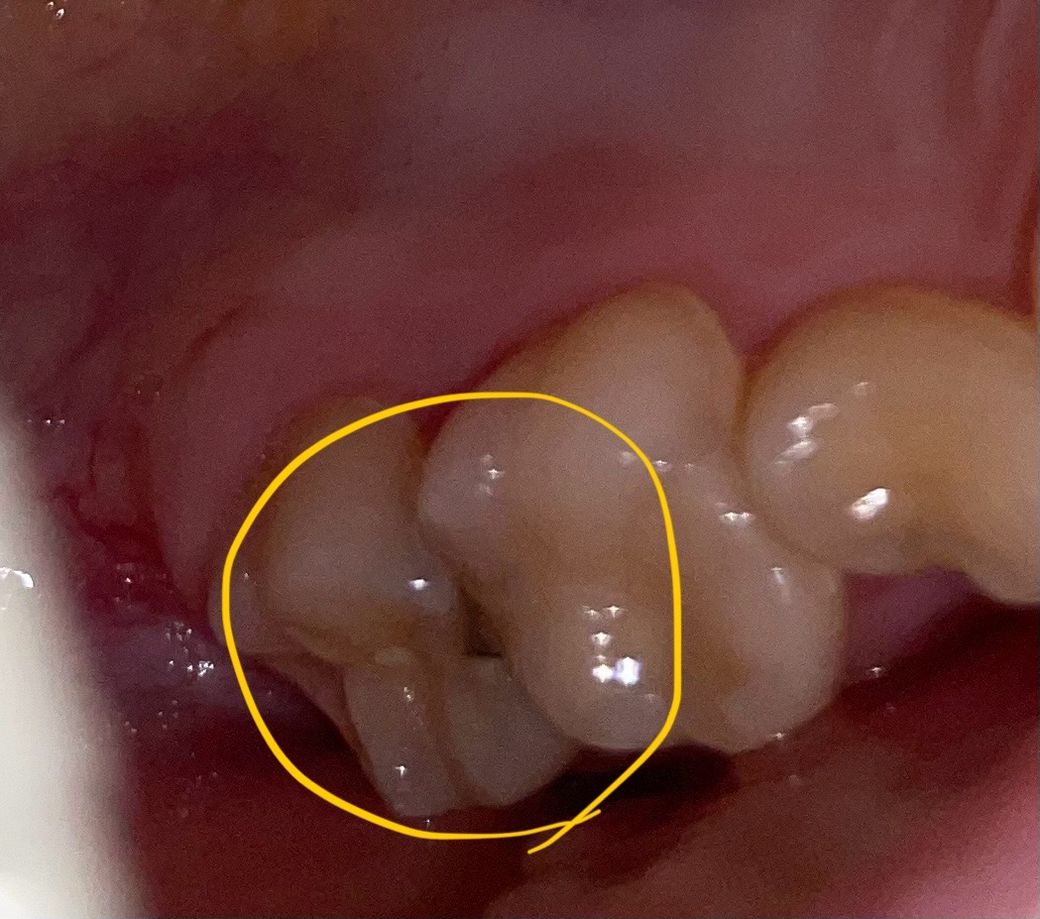

(‼️사진 있습니다) 충치인가요????

어제부터 갑자기 뭐 씹을 때 엄청 아파요

사진의 저 치아인데 충치인 건가요?

1년 전 쯤에 씌운 치아입니다 ㅠㅠ

어느 정도까지 진행된건지 치과 가면 어떤 진료를 받게 될 지 예상이라도 알려주시면 감사하겠습니다..

사진으로 봤을 경우 인접면 충치가 생긴것으로 보입니다. 충치가 생긴경우 치료가 필요할수 있기 때문에 치과에서 진료를 받아보는것이 좋습니다.

사진에 보이는정도면 충치가 상당히 진행된거 같습니다 .엑스레이를 찍어봐야 알겟지만 신경치료를 해야될 가능성이 있어 보입니다.

1. 충치가 맞습니다

2. 옆면이 파고들어가 생긴 충치로 신경치료 가능성 있습니다

3. 치아 옆면은 신경에 가깝기 때문입니다

4. 신경치료는 안해도 된다면 인레이 치료를 합니다